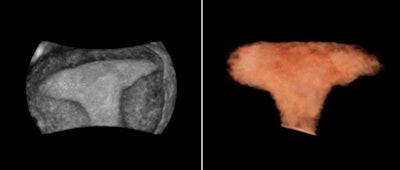

In reproductive medicine, the ovaries are measured to detect abnormalities. Ovarian size can be determined by measuring the ovary in three dimensions (width, length, and depth) on views in two orthogonal planes or by visualizing a 3D volume, according to the 2008 AIUM practice parameter "Ultrasound in Reproductive Medicine."